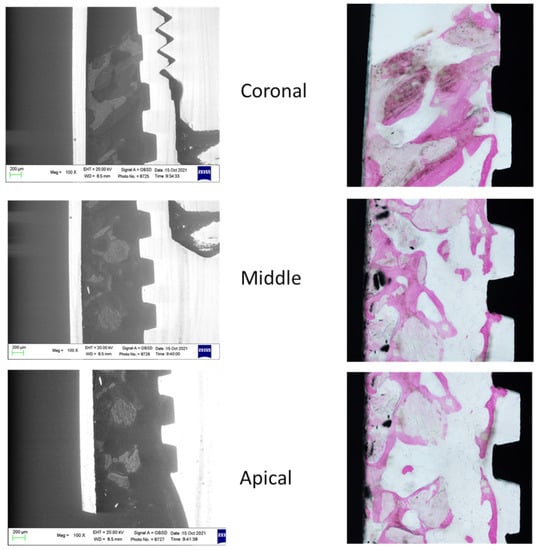

The ESEM-EDX analysis at the coronal, middle and apical ROI of two specimens included in the study is schematized in Figure 3 and Figure 4.

Figure 3. ESEM and OM images were obtained to identify bone tissue and bone grafts around the implant. Original magnification 100×.

Figure 4. ESEM and OM images were obtained to identify bone tissue and bone grafts around the implant. Original magnification 100×.

3.2. Analysis of the Bone Tissues at Coronal, Middle and Apical ROI

Sixteen histological specimens were analyzed using OM and ESEM-EDX. The presence of bone graft granules showed marked variations when considering cortical versus apical and middle ROI. The bone tissue in contact with the granules was still immature. In most cases, bone area 2 was detected along with some bone area 3. Consequently, the bone tissue in the middle and apical bone was characterized as woven bone with low amounts of lamellar bone.

In cortical ROI, bone tissue was mostly compact with no or very low presence of biomaterial granules. High mineralization, detected by high Ca/N and P/N ratios, was observed (Bone Area 3 and 4). Low presence of bone area 2 was reported. In the middle and apical ROI, a high presence of bone area 2 was observed.